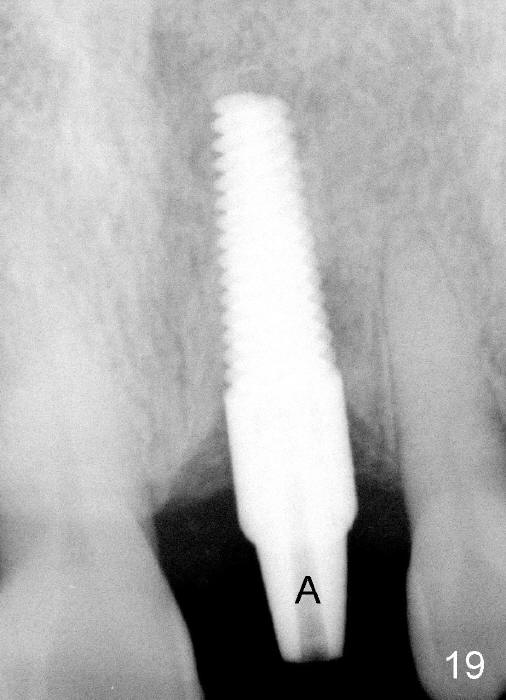

A 60-year-old lady had an abscess mesial to #9 six years ago (Fig.1,2 <), treated as a perio lesion by laser (Fig.3) and osseous surgery without bone graft (Fig.6, followed by CT exam revealing semi-circumferential bone loss (Fig.4,5). When the perio treatment failed, attention was paid to endo aspect (Fig.7-9). In fact the pulp was found to be vital when access to root canal therapy was made. As expected, the treatment failed again. The palatal fistula persisted. The infection was suspected to be a source of remote immediate implant site (#30). The tooth #9 was extracted. It appears that there is a semilunar crack line in the linguomesial root (Fig.12). When the socket healed 2 weeks post extraction (Fig.10), the #30 buccal defect was debrided with bone graft. There was no bone resorption 4 weeks post extraction (Fig.11); a 4.5x17 mm implant was placed (Fig.13-15). An immediate provisional was fabricated (Fig.16-18). Fig.19,20 were taken 3 months post implantation and 7 months post cementation, respectively. Dense bone forms around the implant coronally 4 years 5 months post cementation (Fig.21), while the gingiva is healthy palatally (Fig.22) and buccally (Fig.23).